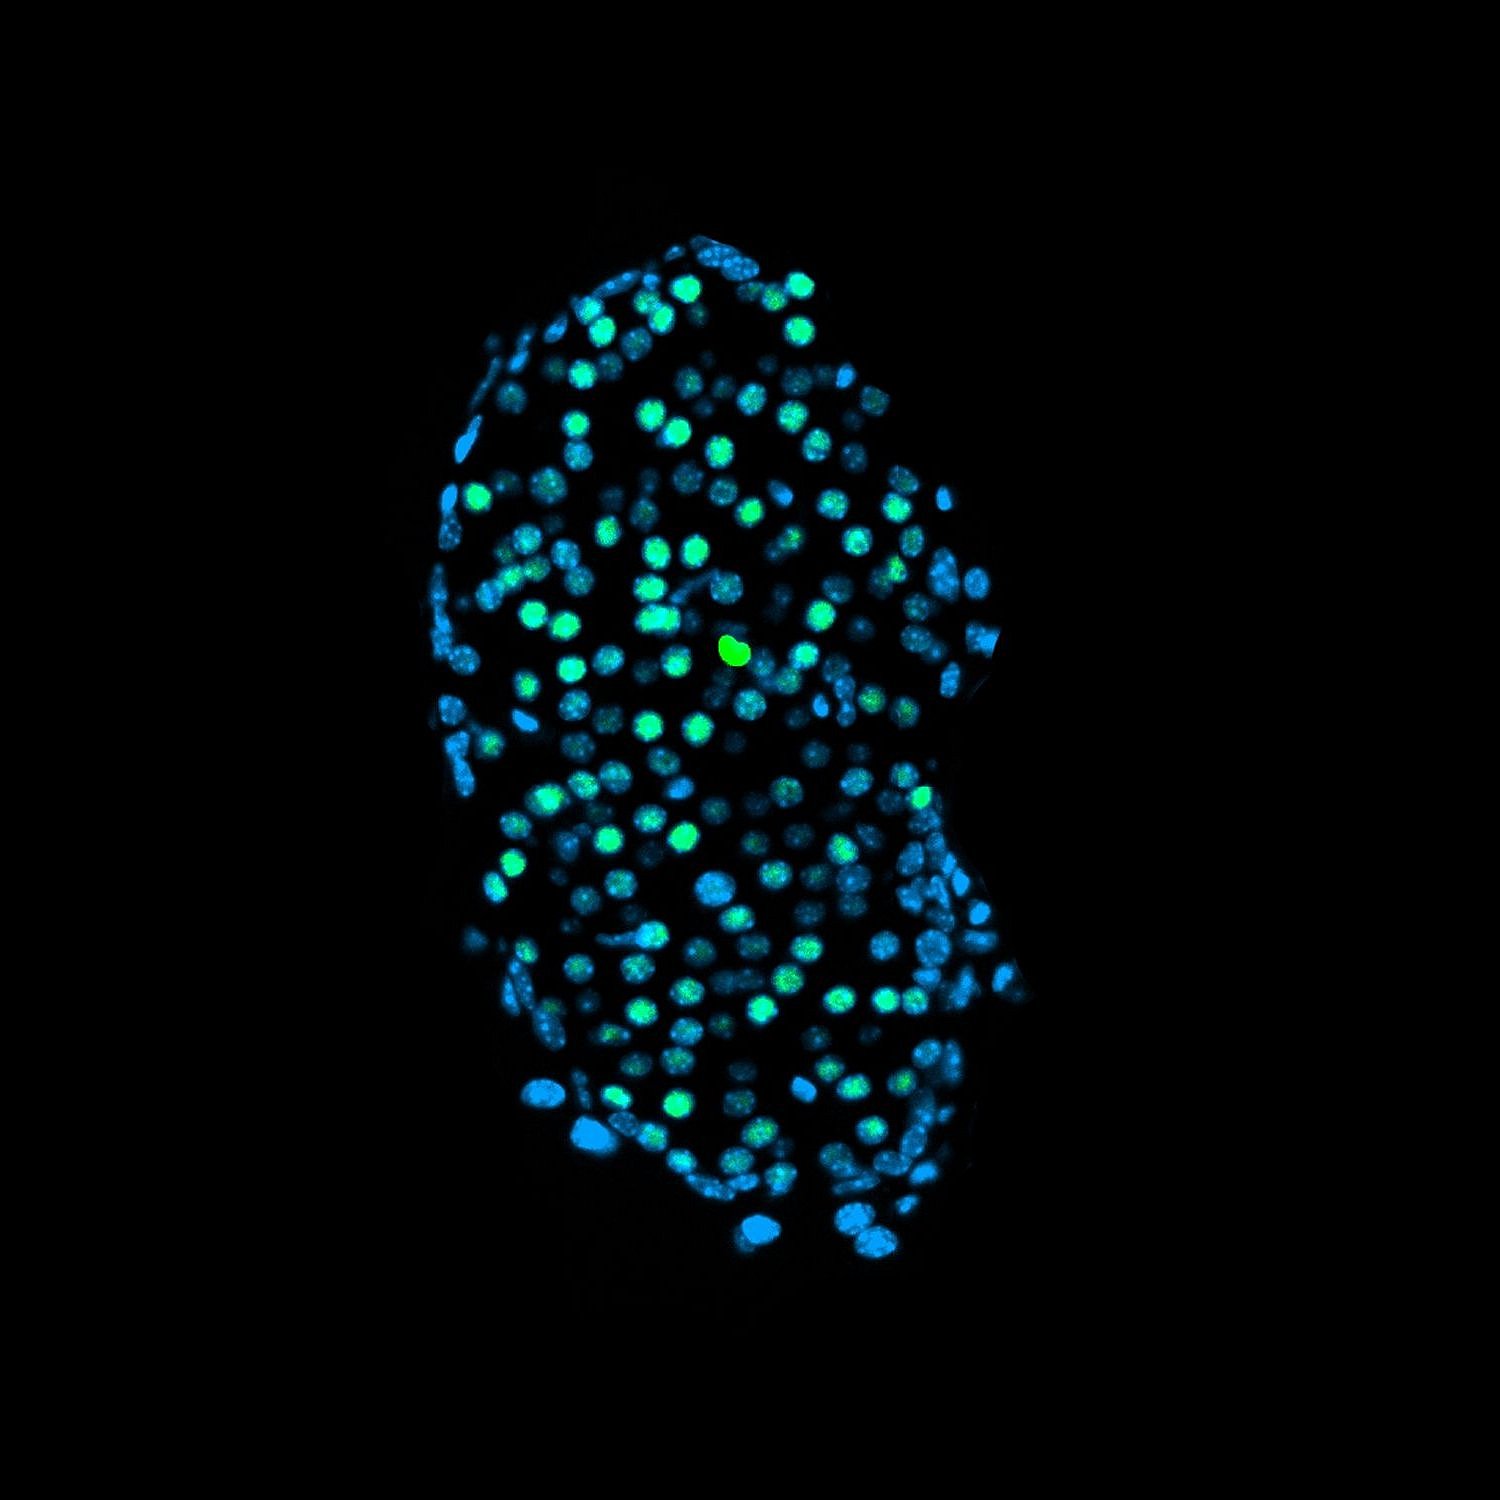

Bei den heranwachsenden Tieren hingegen arbeiteten die Beta-Zellen der Bauchspeicheldrüse nur noch eingeschränkt. Da diese für die Produktion des essenziellen Hormons Insulin verantwortlich sind, hat das schwerwiegende Folgen und führt langfristig zu Diabetes. Hierbei produziert der Körper zu wenig Insulin und der Stoffwechsel gerät aus dem Gleichgewicht. „Intervallfasten wirkt sich eigentlich positiv auf die Beta-Zellen aus. Dass in der Mausstudie junge Tiere nach dauerhaftem Intervallfasten dann weniger Insulin produzierten, hat uns deshalb überrascht“, erklärt Leonardo Matta von Helmholtz Munich, einer der Erstautoren der Arbeit.

Defekte Beta-Zellen ähneln denen von Typ-1-Diabetes-Betroffenen

Warum das passiert, konnten die Forschenden mithilfe der hochauflösenden Einzelzellsequenzierung entschlüsseln. Sie untersuchten den Bauplan der Zellen der Bauchspeicheldrüse und fanden heraus, dass sich die Beta-Zellen der jungen Tiere nicht richtig entwickelten: „Die Zellen der heranwachsenden Mäuse hörten an einem bestimmten Punkt auf zu reifen und produzierten dann weniger Insulin“, sagt Peter Weber von Helmholtz Munich, ebenfalls Erstautor der Studie. Die älteren Tiere, deren Zellen schon vor Beginn des Intervallfastens ausgereift waren, waren davon nicht betroffen.

Die Forschenden verglichen diesen Befund mit Referenzdaten aus menschlichen Geweben. Patientinnen und Patienten mit Typ-1-Diabetes, bei denen die Beta-Zellen durch eine Autoimmunreaktion verloren gehen, zeigten ähnliche verminderte Reifungsmuster wie die der jungen Tiere. Dies unterstreicht die Forschungsergebnisse der Mausstudie und stützt die These des Teams, dass die Ergebnisse auf den Menschen übertragbar sind.